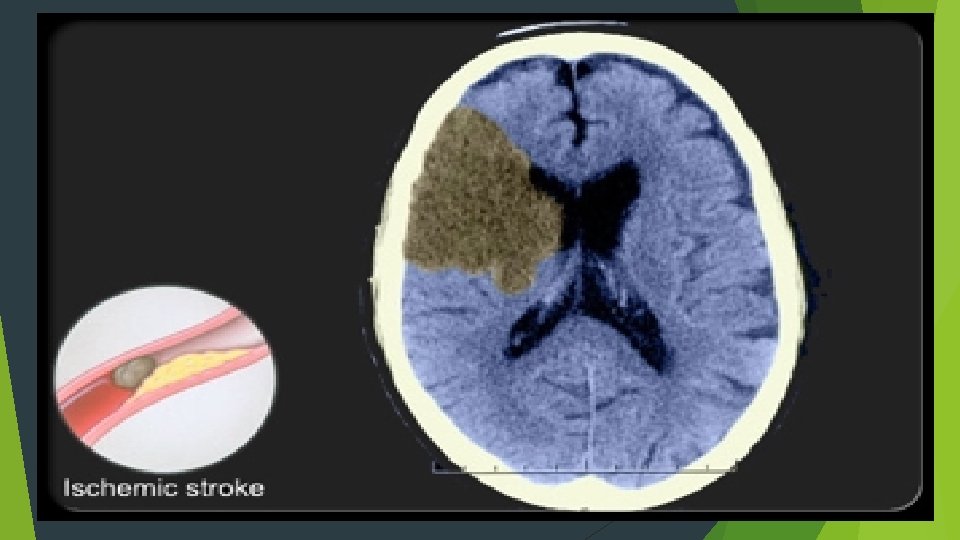

CLASSIFICATION Ischemic Stroke 87% 80% thrombotic 20% embolic Hemorrhagic Stroke 13% 97% intracerebral 3% subdural

IMAGING CT…reliable for intracranial hemorrhage close to 100% sensitive not sensitive for ischemic CVA…especially early MRI…diffusion weighted hyperdense regions of ischemia can detect ischemia after 5 -10 minutes time consuming…. cooperation issues ECHO…echocardiography can identify source of cerebral emboli identify patent foramen ovale